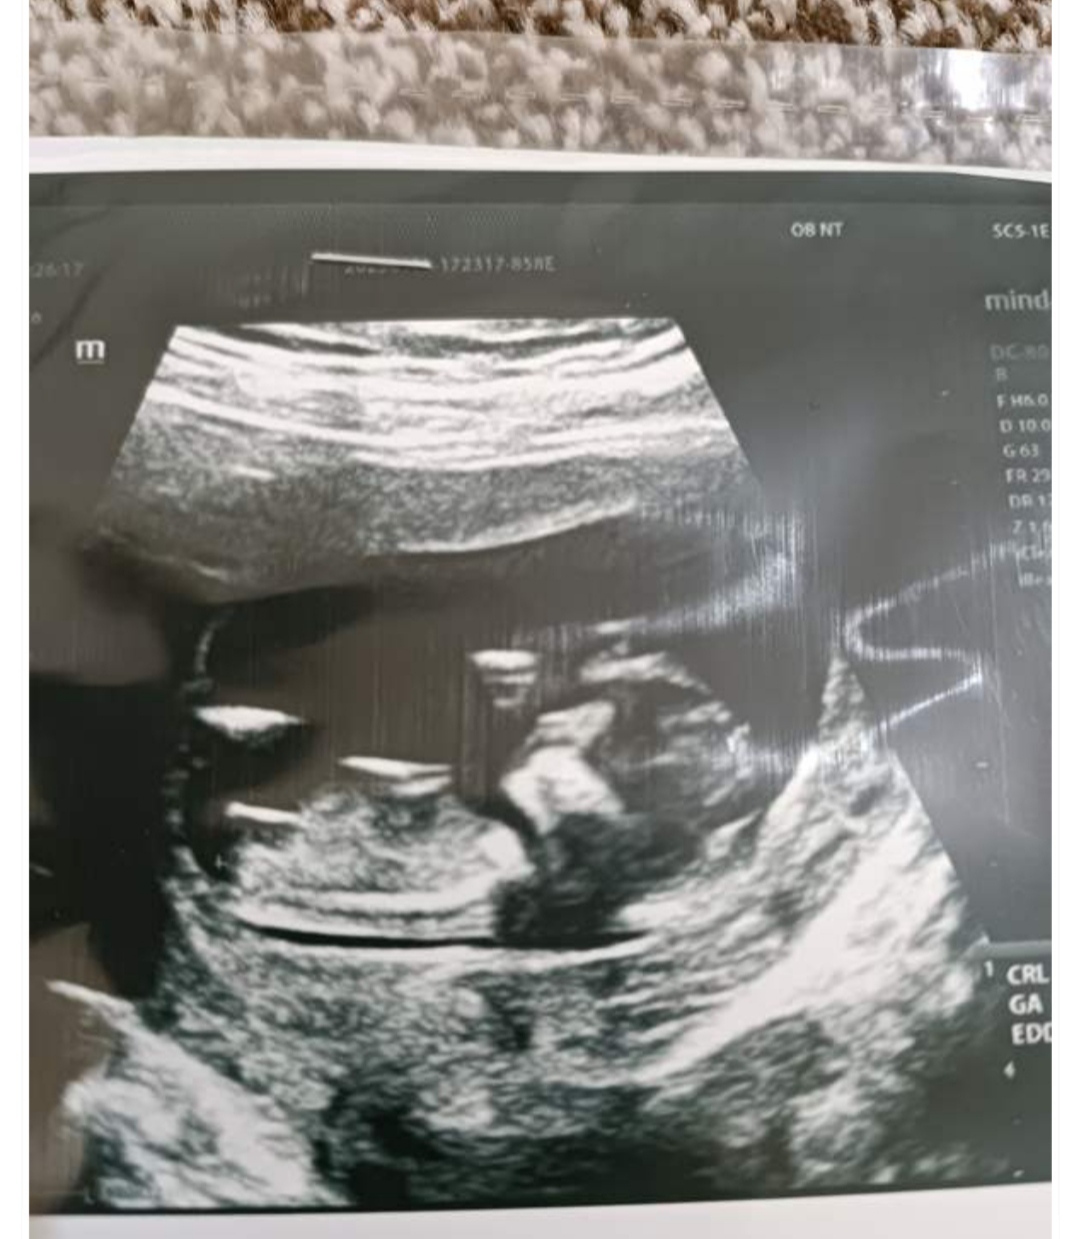

سلام دوستان گلم ،دوازده هفتگی ان تی داده بودم جنسیت رو هفتاد درصد گفت دختره ،ماهم رفتیم اکثر وسایلا رو صورتی خریدیم ،  جواب سل فریم امروز اومد نشون دکترم دادم و گفت جنسیت پسره ،گفت هیجده هفتگی برو برای آنومالی ،منتظر میمونم آنومالی رو ببینم بعد مطمعن بشم برم ببینم تعویض میکنن صورتی ها رو ؟اگه نکردن برم آبی بخرم باز😂خلاصه جنسیت نی نی مون فعلا پسره😂😂😂

عکس ان تی بفرستم میتونی بفهمی عزیزم؟